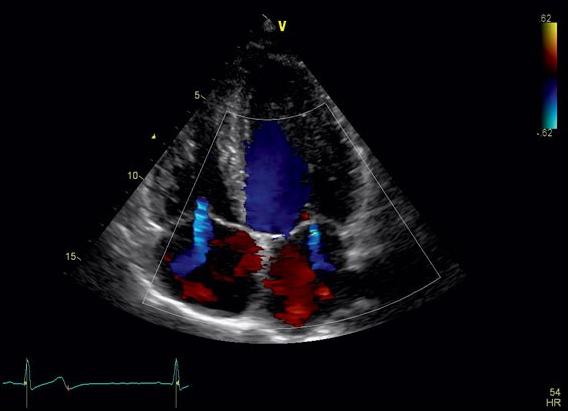

УЗ-диагностика сердца часто дополняется допплерографией ― методом определения скорости движения крови в сосудах. Этим обеспечивает возможность:

• показать движение крови по камерам сердца;

• определить функционирование коронарных артерий (обеспечивающих кровоснабжение самого сердца), легочного ствола, аорты, воротных и легочных вен.

• Дефекты межжелудочковой и межпредсердной перегородки – визуализируются в режиме цветового допплера, как потоки крови в проекции участков соответствующих перегородок.

• Аномалии клапанов оцениваются в В, М – режимах. Клапанный кровоток и степень регургитации обязательно фиксируется в режиме цветового или импульсного допплера.